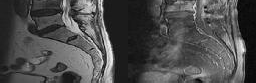

Figures 1 and 2 depict the MRIs of a 39-year-old woman with severe right

leg pain and mild back pain. Symptoms have been present for 3 months. She has tried physical therapy and received transforaminal injections and oral pain medications with minimal relief. She is offered a lumbar microdiskectomy. During the procedure, she sustains an incidental durotomy which is repaired primarily. She is informed that the rate of reoperation following lumbar microdiskectomy is

Discussion: B

Recurrent disk herniation and reoperations are common complications following lumbar microdiskectomy. In the Spine Patient Outcomes Research Trial, the reoperation rate following diskectomy was 15% at 8-year follow-up. In this same cohort, no long-term impact of incidental durotomies was sustained during these procedures.